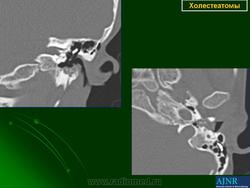

Диагностика холестеатомы представляет определенные трудности. Основными методами выявления холестеатомы последние несколько десятилетий остаются отоскопия (отомикроскопия) и рентгенологические методы (рентгенография в различных укладках и компьютерная томография). Компьютерная томография височных костей позволяет диагностировать холестеатому намного чаще, чем обычная рентгенография, однако степень достоверности данной диагностики остается невысокой, так как плотность холестеатомы практически соответствует плотности грануляционной ткани. Поэтому чувствительность метода КТ в диагностике холестеатомы составляет всего 71% при специфичности 55% [50]. Кроме того, следует учитывать, что указанный метод требует не только дорогостоящего оборудования, но и высококвалифицированных рентгенологов со специальной подготовкой, позволяющей им правильно интерпретировать полученные результаты.

2. Применение компьютерной томографии позволяет повысить степень обнаружения патологического процесса до 90% случаев, однако не позволяет достоверно дифференцировать холестеатому и грануляционную ткань по причине низкой специфичности метода (55%).